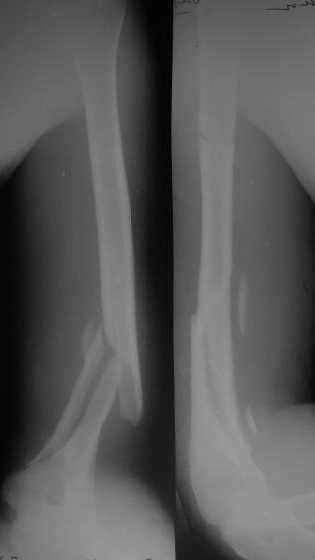

Огромное спасибо всем принимающим участие в дискуссии. Вначале отвечу на поступавшие персональные вопросы: 1. обстоятельства травмы - соревнования по армрестлингу (от себя замечу, что у военных нередкая травма в последнее время! На мой взгляд это связано с вовлечением в это дело неподготовленных людей - командирам нравится, т.к. в плане реквизита намного легче организовать чем традиционное перетягивание каната...). 2. в отношении провокационной составляющей - она присутствует, но лишь в той степени в какой любое инициирование дискуссии несет в себе элемент провокации... 3. про актуальность консервативного лечения - мне кажется это актуально всегда и при любой локализации если врач владеет методом, например, часто наблюдал великолепные функциональные результаты консервативного лечения переломо-вывихов голеностопных суставов... Тут только надо помнить, что "консервативное" это тоже лечение (контроль, тяги, перекладывание повязок), а не просто накладываем гипс и через энное время говорим, что не получилось и берем на операцию.

Теперь непосредственно по больному. Лечим функциональной повязкой, добились вот чего (приложение). Будем признательны за дальнейший комментарий - мое мнение, что можно продолжить без операции.